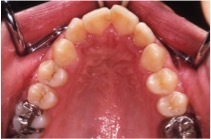

上あごの狭窄と高口蓋

指を吸う力により、上あごの歯列が狭くなり(狭窄)、歯列の形がV字型に変形します。このため、上あごの内側(口蓋)のくぼみが深くなります。高口蓋(こうこうがい)といいます。

下あごの偏位

上あご歯列の狭窄により、上あごと下あごの歯列の幅が合わなくなると、左右どちらかに下あごを偏位させてかむようになります。左の写真は下あごを右(本人の右側)に偏位させて咬んでいます。

左上に載せた開咬の写真では、上あごと下あごの歯列の幅に差がないことがわかります。さらに上あご歯列が狭窄すると、下あごを左右どちらかに偏位させてかまざるを得なくなるのです。